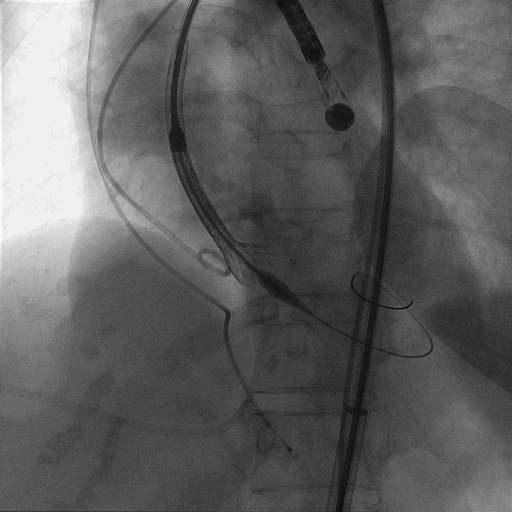

术中造影

植入L26 VenusA-Plus瓣膜,标准位释放,释放到2/3,观察瓣膜位置,以及再次确认冠脉风险,左冠正常显影,选择全部释放。